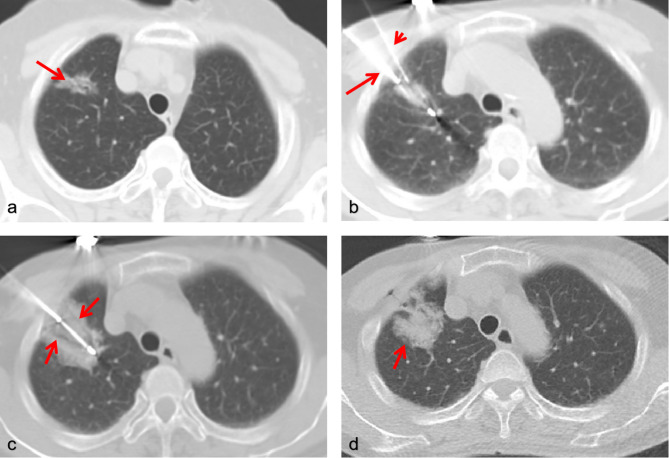

Methods: This retrospective study involved 124 patients with 131 highly suspicious malignant pulmonary nodules. Patients either underwent synchronous percutaneous core-needle biopsy and cryoablation (Group A) or separately underwent these procedures (Group B) from December 2020 to May 2024. All procedures were performed under CT guidance using a percutaneous approach. We analyzed technical success rates, complications, diagnostic yield, and local tumor control.

Results: Technical success rates were 100% in both groups. The rate of pneumothorax was 42.1% (16/38) in Group A and 34.9% (30/86) in Group B. In Group A, hemoptysis and pleural effusion rates were 18.4% (7/38) and 23.7% (9/38), respectively, while in Group B, these rates were 16.3% (14/86) and 12.8% (11/86). These differences were not statistically significant. The diagnostic positive rate in Group A was 87.5%. The mean follow-up duration was 11.8 months (95% confidence interval [CI], 10.2-13.4), with local tumor control rates of 97% for Group A and 88% for Group B. The effectiveness rates of synchronous and separate procedures were similar.

Conclusion: Synchronous biopsy-ablation is an effective method for obtaining tumor pathology and local treatment of lung tumors simultaneously. It is a viable option for select patients where expedited diagnosis-therapy is clinically justified, particularly when molecular profiling is not immediately indicated.